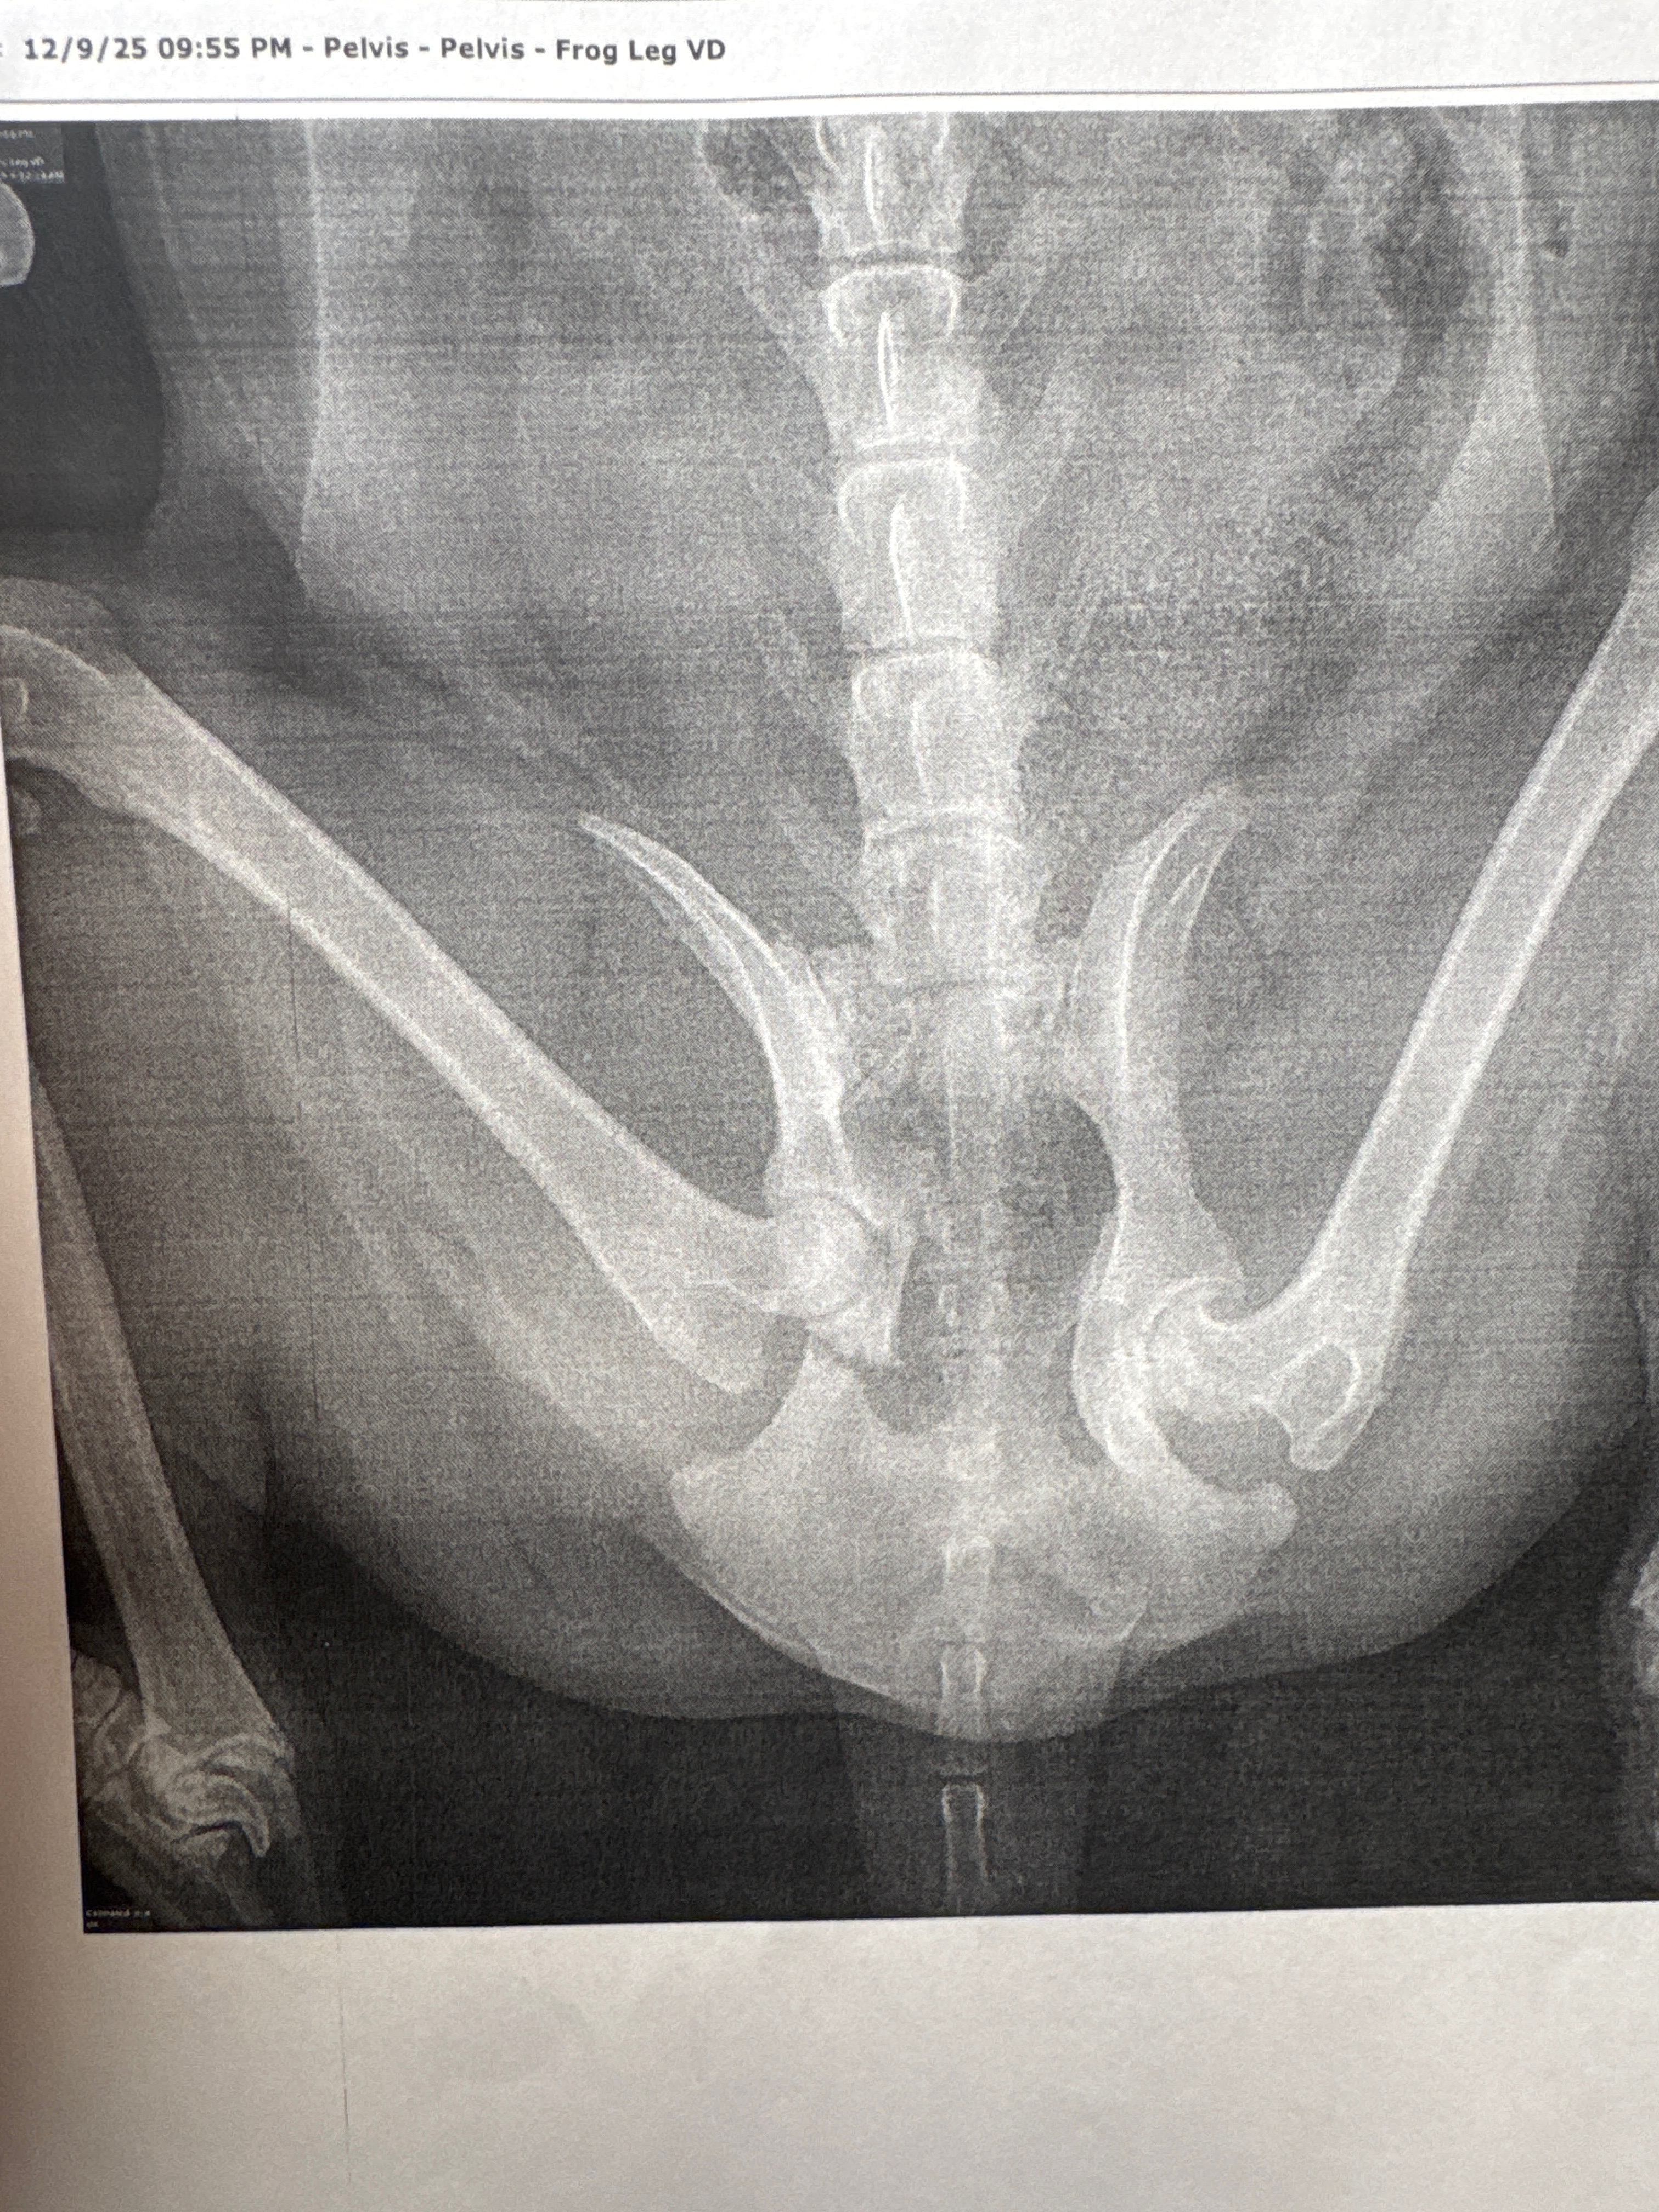

Felix is alive, but he suffered a broken hip in two places and now needs major surgery to recover. The veterinary team will need to place screws, a plate, and other hardware to help his hip heal correctly. This isn’t the first time Felix has faced something like this. He was hit once before in 2018, but we couldn’t afford surgery then. This time, we’re determined to give him the best chance at a full recovery. However, the costs for surgery, medications, and follow-up appointments are overwhelming. Felix is the sweetest boy, always patient with our daughter and still so gentle and loving, even after all he’s been through. We’re doing everything we can to cover this unexpected expense, but we can’t do it alone. Any support, whether it’s a donation, sharing our story, or sending kind words, would mean the world to us. Thank you for helping Felix heal and for being part of his journey back home. ❤️❤️